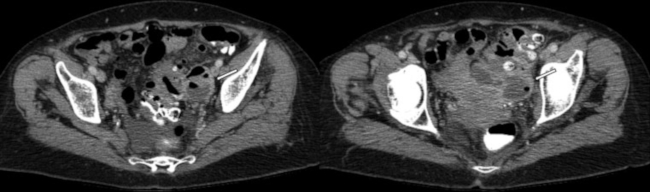

Clínicamente, dicho cuadro se caracteriza por dolor abdominal a predominio del cuadrante inferior izquierdo y fiebre, acompañado de alteración en los parámetros de laboratorio vinculables a un proceso infeccioso. En caso de complicaciones, puede progresar a un cuadro de peritonitis, presentando mal estado general, dolor a la descompresión, defensa abdominal. En ocasiones, se asocia además a hemorragia digestiva baja, estenosis post diverticulitis aguda, debiendo realizar el diagnóstico diferencial con patología neoplásica.6 Cuando la afectación compromete el colon derecho, clínicamente el cuadro es indistinguible de la apendicitis aguda, siendo los estudios por imágenes indispensables para un correcto diagnóstico (►Fig. 1).7

Estadio IA: Pequeñas burbujas de aire pericólicas o presencia de líquido libre pericólico sin absceso. Se recomienda tratamiento con antibióticos intravenosos u orales y observación hospitalaria (►Fig. 1).